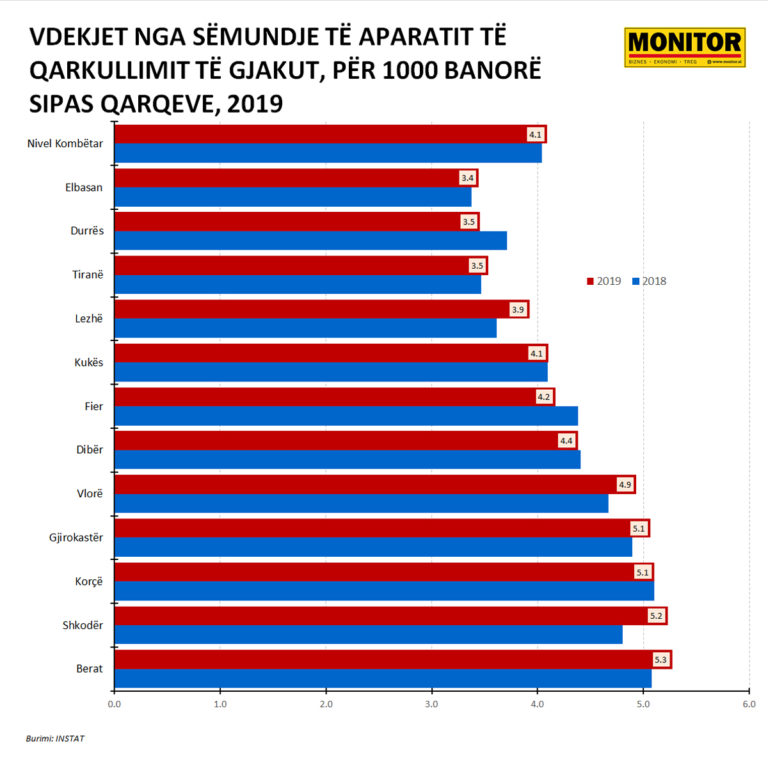

Berati me zemrën më të dobët, rritet Shkodra

Në të gjithë vendin, në 2019-n kishte 4.1 vdekje për 1000 banorë, për sëmundjen e aparatit të qarkullimit të gjakut, me një rritje të lehtë në raport me 4, që ishte ky tregues një vit më parë.

Sipas qarqeve, qyteti me vdekjet më të larta nga zemra dhe tensioni, në raport me popullsinë është Berati, me 5.3 vdekje për 1000 banorë, me rritje në raport me vitin e mëparshëm (shih grafikun).

Në vend të dytë ka kaluar Shkodra, e cila ka shënuar një rritje të lartë të humbjeve të jetës nga zemra dhe tensioni në 2019-n (+8%), me 77 jetë të humbura më shumë, duke u ngjitur në 5.3 vdekje për 1000 banorë, nga 4.8% që ishte ky tregues vitin e mëparshëm.

Më pas renditen Korça e Gjirokastra (5.1 secili) , Vlora (4.9), Dibra (4.4).

Zemrën më të fortë e kanë tiranasit (3.5 vdekje për 1000 banorë), durrsakët (po 3.5) dhe elbasanllinjtë (3.4).